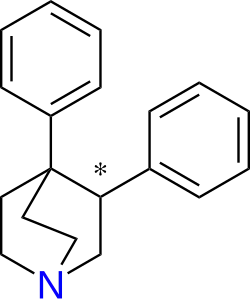

(+)-CPCA ("nocaine")[190] is the 3R,4S piperidine stereoisomer of (phenyltropane based) RTI-31.[191] It is non addictive, although this might be due to it being a NDRI, not a SNDRI. The β-naphthyl analog of "Nocaine"[112] is a SNDRI though in the case of both the SS and RR enantiomers. Consider the piperidine analogs of brasofensine[79] and tesofensine.[192] These were prepared by NeuroSearch (In Denmark) by the chemists Peter Moldt (2002),[193] and Frank Wätjen (2004–2009).[194][195] There are four separate isomers to consider (SS, RR, S/R and R/S). This is because there are two chiral carbon sites of asymmetry (means 2 to the power of n isomers to consider where n is the number of chiral carbons). They are therefore a diastereo(iso)meric pair of racemers. With a racemic pair of diastereomers, there is still the question of syn (cis) or anti (trans). In the case of the phenyltropanes, although there are four chiral carbons, there are only eight possible isomers to consider. This is based on the fact that the compound is bicyclic and therefore does not adhere to the equation given above.

It is complicated to explain which isomers are desired. For example, although Alan P. Kozikowski showed that R/S nocaine is less addictive than SS Nocaine, studies on variously substituted phenyltropanes by F. Ivy Carroll[196] et at. revealed that the ββ isomers were less likely to cause convulsions, tremor and death than the corresponding trans isomers (more specifically, what is meant is the 1R,2R,3S isomers).[197] While it does still have to be conceded that RTI-55 caused death at a dosage of 100 mg/kg, its therapeutic index of safety is still much better than the corresponding trans isomers because it is a more potent compound.